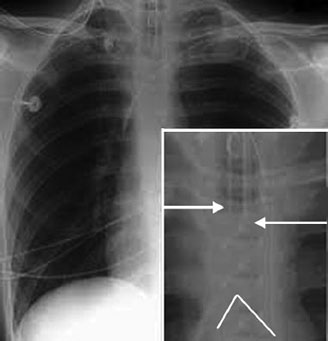

- The endotracheal tube (ETT) in an adult should lie 1–2 cm superior to the carina (Fig. 17)

- On an X-ray the carina is the point at which the trachea can be seen dividing into the right and left bronchi—around T4.